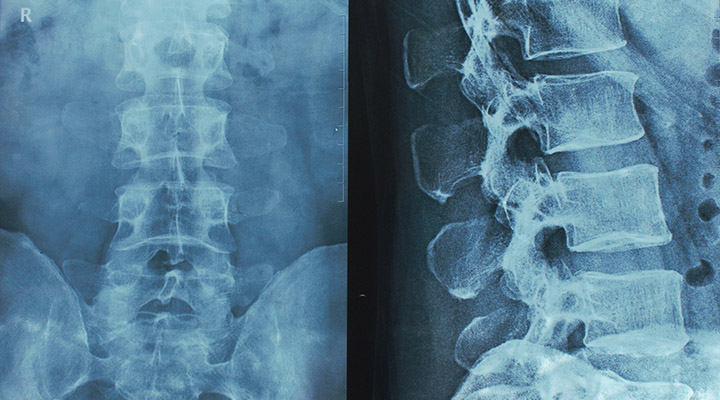

脊椎外科

首から腰までの脊椎疾患を専門医が診療。ヘルニアや狭窄症などに、保存療法から手術まで検討し、痛み・しびれの軽減と生活機能の維持・改善を支援します。